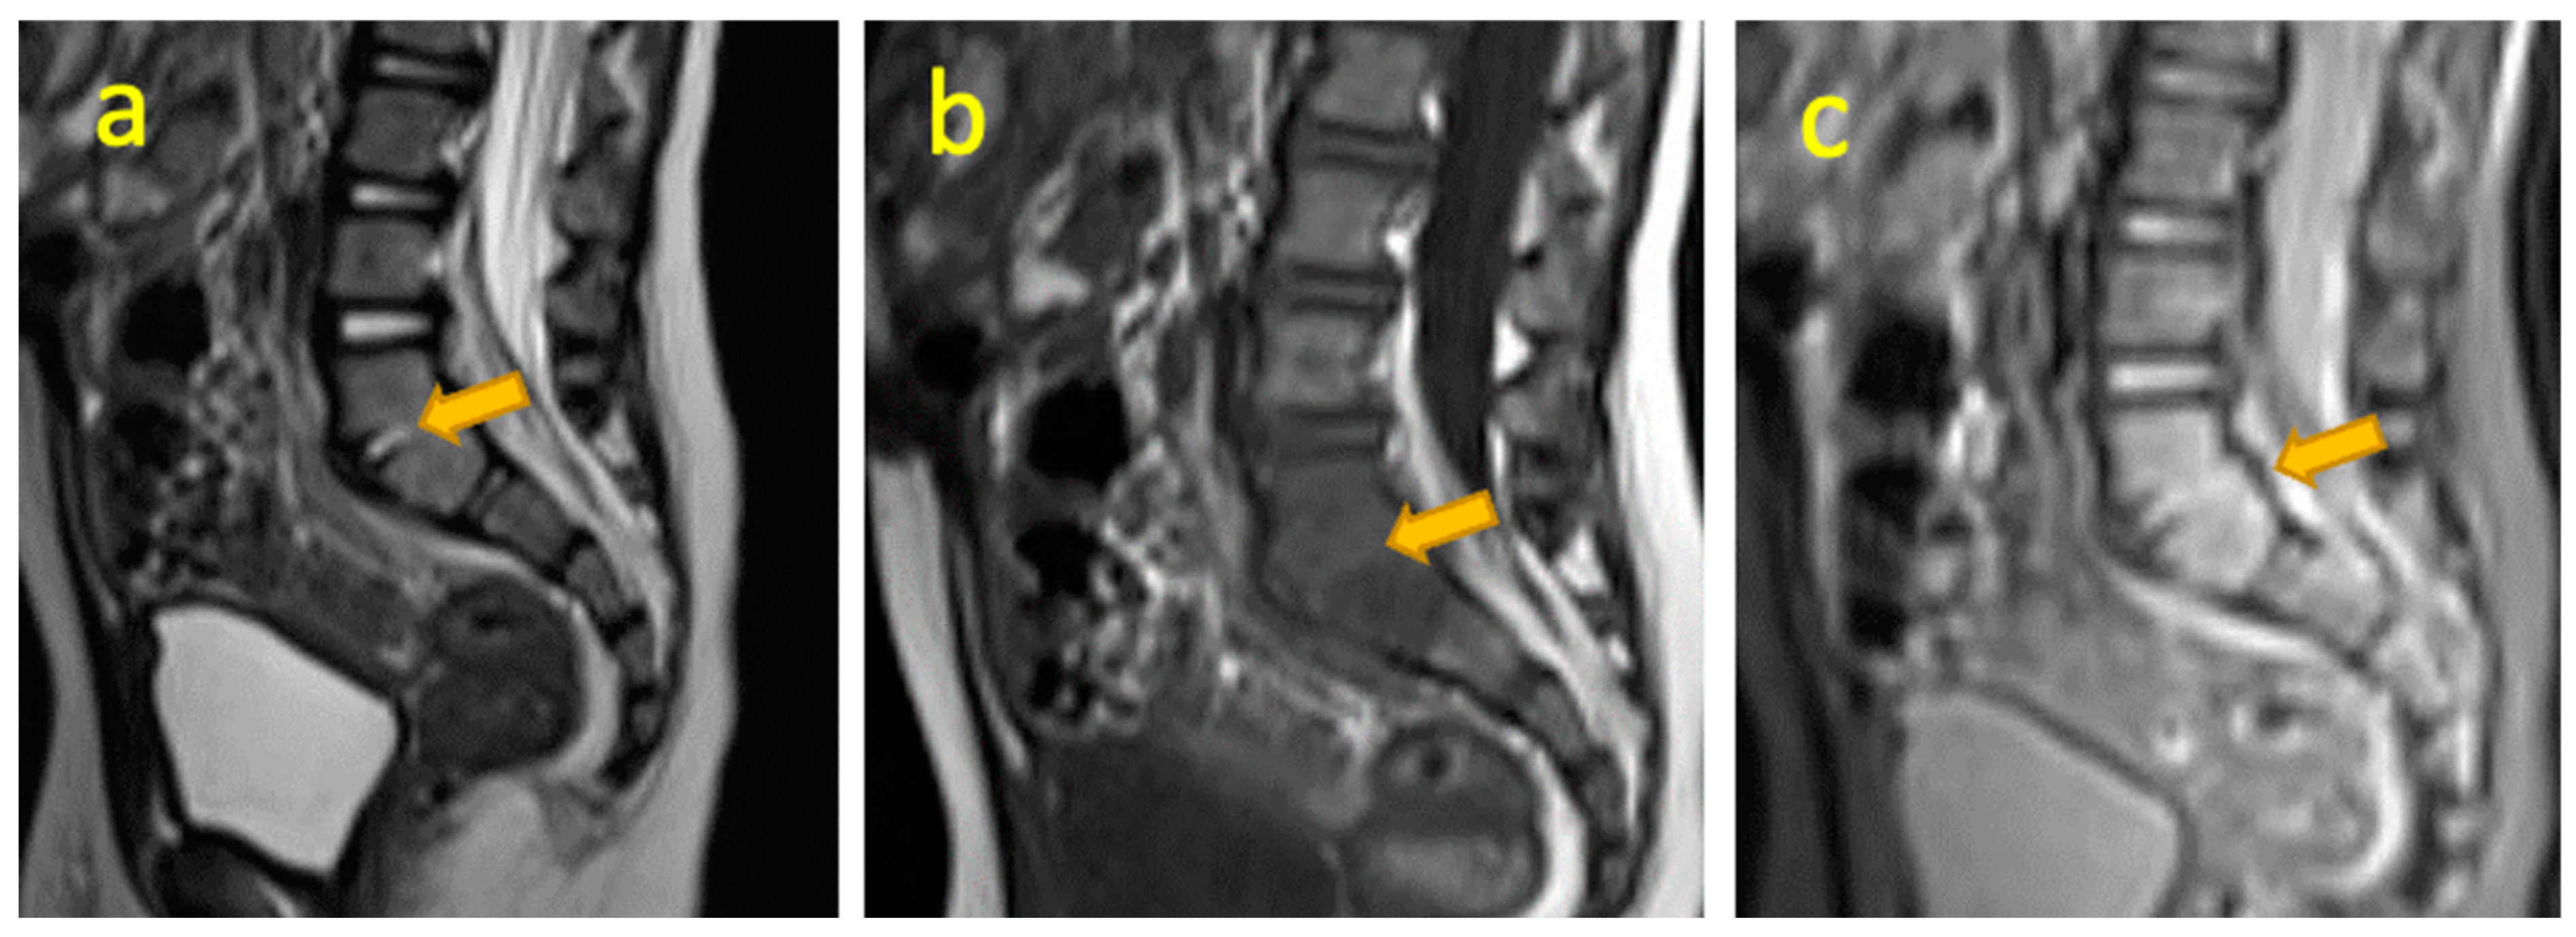

14. Lumbar Spine Discitis